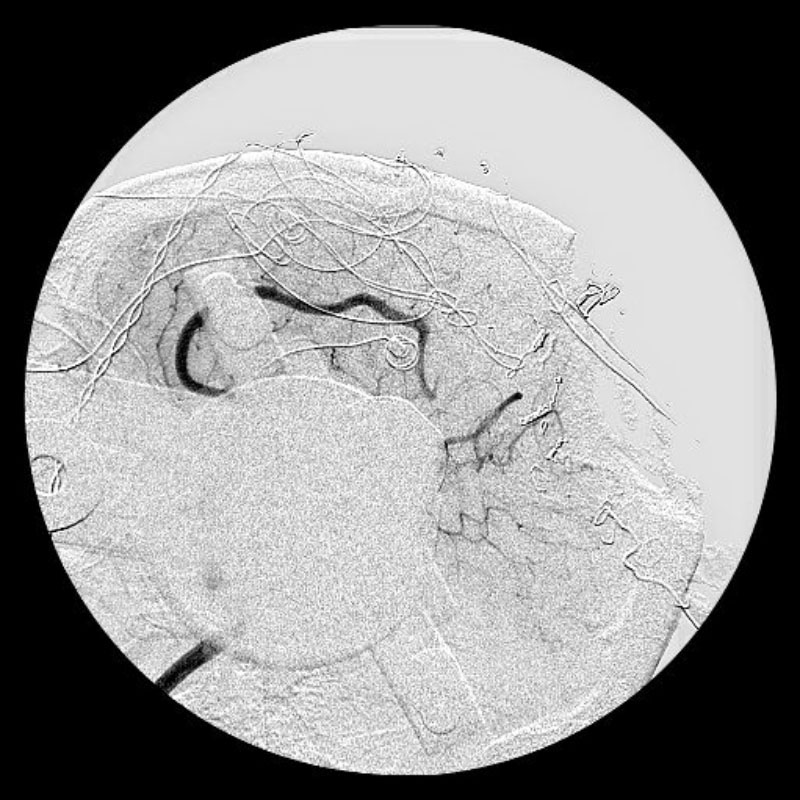

'19年5月

30代

富永/久貝

右中小脳脚 出血再発

SM 3(S1,E1,V1)

米国の病院

No.359 モニタリング

No.359 手術前

No.359 手術中

No.359 手術後

出血既往があり。2回の手術前血管内手術の後に、

Lateral transpeduncular approachにより再々出血予防を目的に

摘出手術を行う。完全摘出であることを確認した。

手術による合併症や後遺症なしで退院した。経過良好。